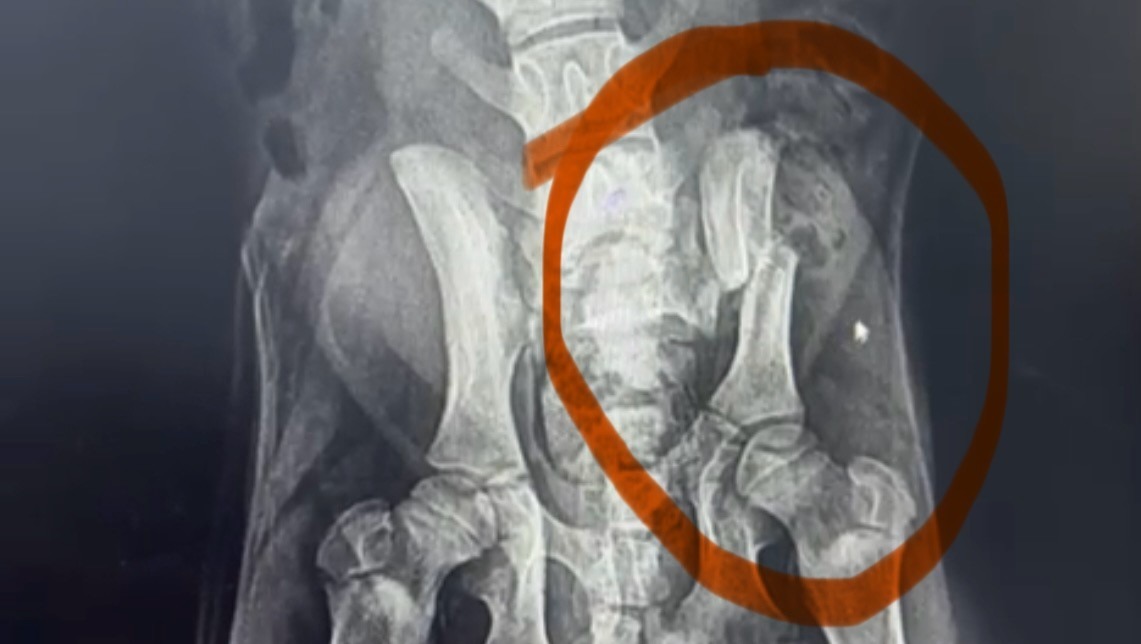

Comme vous pouvez le voir les animaux que nous aidons sont victimes de graves blessures nécessitant des soins vétérinaires très importants.

Ces chiens sont handicapés à vie — certains ont perdu une patte, d’autres deux, certains vivent avec une mâchoire arrachée ou la colonne vertébrale brisée. Malgré leur souffrance, ils nous montrent chaque jour leur incroyable courage et leur soif de vie.